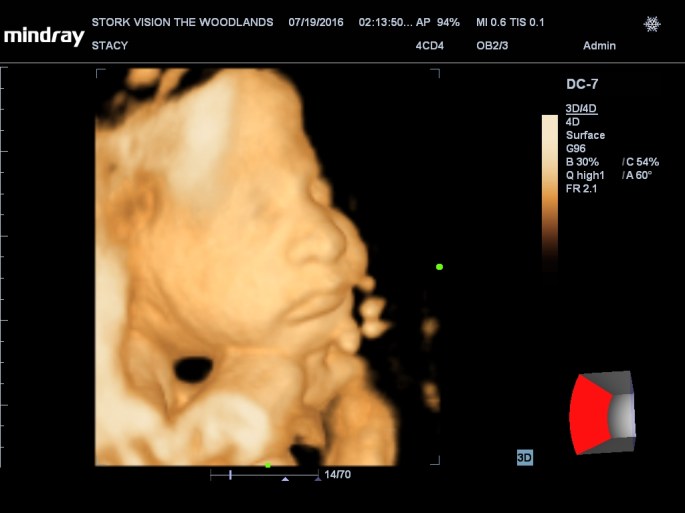

Best moment the week: Seeing Juliette on the 3D/4D ultrasound. So amazing!

Gender: GIRL!